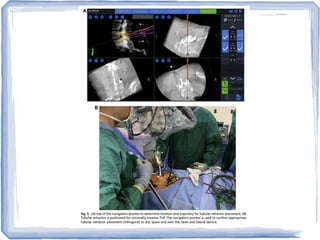

 Mazor Robotics' Renaissance (FDA approved)

 Workstation

 Planning software

 Guidance unit which moves in all planes

 Spinal mounting platforms

Surgical Technique

 Preparation of robot (3D CT, planning)

 Patient positioning

 Attaching the universal image adaptor to C arm

 Affixing clamp and taking AP and 60' oblique

views

 Assembling bridge and preparing and activating

the device

 Approach

 Take the arm indicated by software, align holes

of the arm plate with the pins of the device

 Make incision with the scalpel through arm tube

 Insert cannula into arm tube, push and rotate blunt

trocar

 Drill guide in cannula, drill bit in the guide,

reduction tube in the drilled hole

 Insert guidewire, split muscle with dilators, and

insert the screws